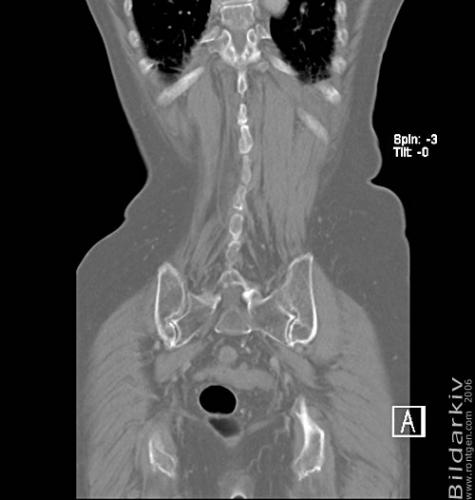

CT colon 43

Datortomografi av tjocktarmen (colon) med infunderad luft i tarmen samt med kontrast i blodbanan. Koronar bildserie.

CT multislice 16